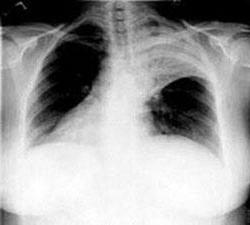

Рентгеногрфия грудной клетки в двух проекциях (прямой и боковой). При пневмониях видны очаговые затемнения, либо долевые.

Оба типа заболевания не представляют опасности для окружающих, диагностируются только с помощью рентгена и требуют особого лечения.